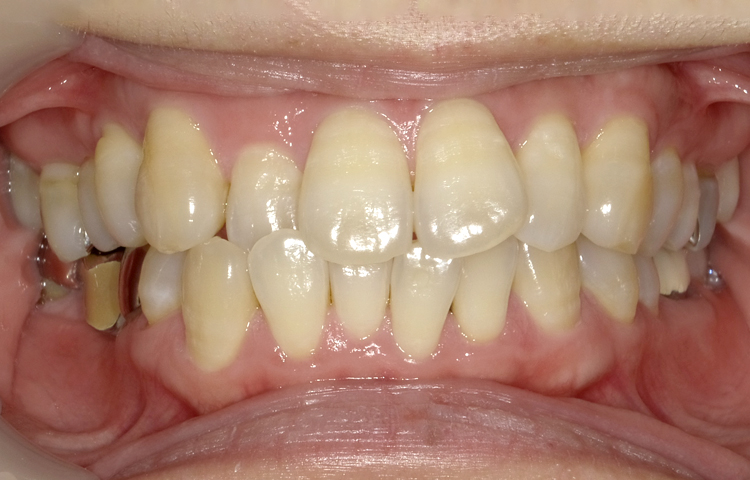

症例7

治療前

治療後

| 主訴 | 前歯2本出ているのが気になる |

|---|---|

| 治療 期間 |

約9ヶ月 |

| 治療費 | 412,500円(税込)/調整費用別途 |

| 治療 内容 |

上下の前歯部にワイヤーを着けて進めていく、プチ矯正で施術。 |

| 治療の リスク |

奥歯を動かさないので前に出して並べていく。 歯を動かすことで、歯茎が下がるリスクある。 装置による清掃の難しさから、歯肉炎や歯周病、虫歯のリスクが高まる。 矯正終了後は、リテーナーを使用し、後戻りを防ぐ必要がある。 |